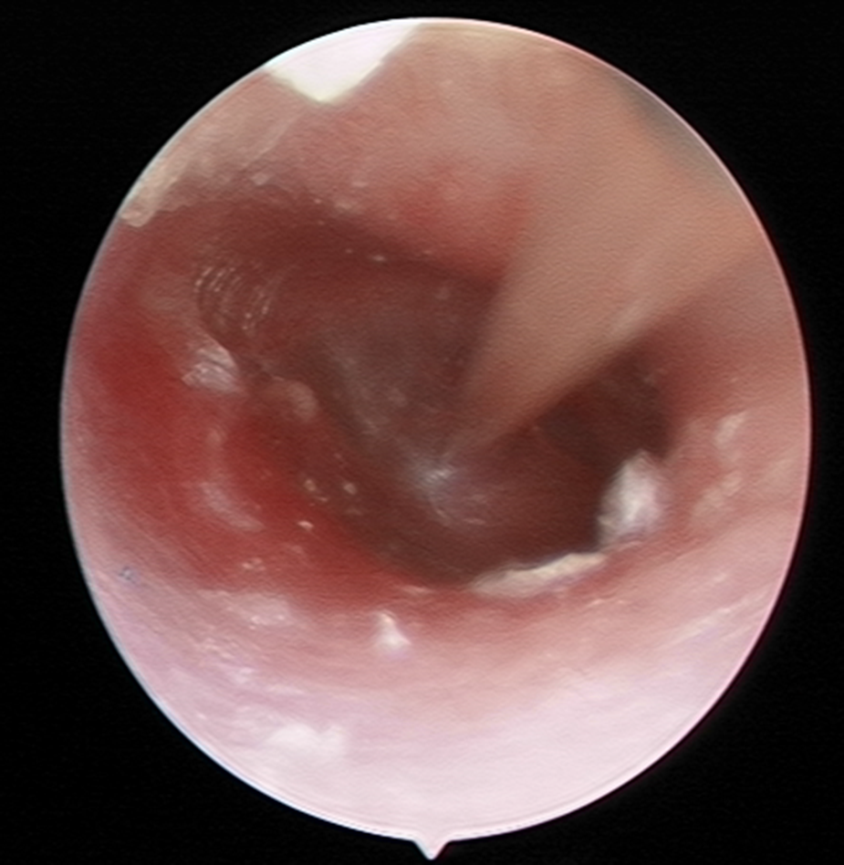

在体格检查时,可能会看到鼓膜内陷,鼓室积液时鼓膜呈毛玻璃样。黄、橙红油亮或琥珀色,慢性者可呈灰蓝或乳白色。浆液性者可透过鼓膜见到液平面。咽鼓管吹张后气泡可增多。

图片

2分泌性中耳炎内镜检查显示鼓膜内陷,光锥缩短。